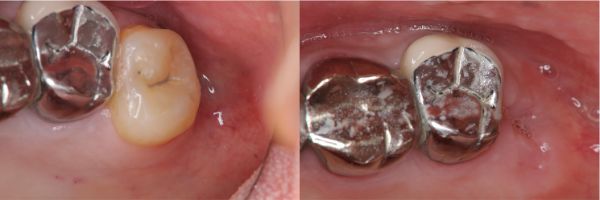

拔牙後傷口處理-阻生齒蛀牙-#48

口腔外科

拔牙後傷口處理